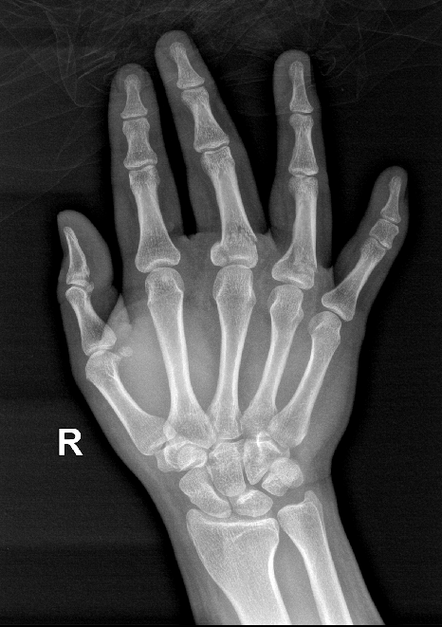

来医院急诊就诊,行x线片提示有右手中指第1节指骨近端骨折,涉及到关节